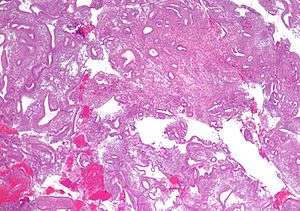

| Micrograph showing simple endometrial hyperplasia, where the gland-to-stroma ratio is preserved but the glands have an irregular shape and/or are dilated. Endometrial biopsy. H&E stain. | |

Like other hyperplastic disorders, endometrial hyperplasia initially represents a physiological response of endometrial tissue to the growth-promoting actions of estrogen. However, the gland-forming cells of a hyperplastic endometrium may also undergo changes over time which predispose them to cancerous transformation. Several histopathology subtypes of endometrial hyperplasia are recognisable to the pathologist, with different therapeutic and prognostic implications.[1] The most commonly used classification system for endometrial hyperplasia is the World Health Organization system, which has four categories: simple hyperplasia without atypia, complex hyperplasia without atypia, simple atypical hyperplasia and complex atypical hyperplasia.[2]

- Endometrial hyperplasia (simple or complex) - Irregularity and cystic expansion of glands (simple) or crowding and budding of glands (complex) without worrisome changes in the appearance of individual gland cells. In one study, 1.6% of patients diagnosed with these abnormalities eventually developed endometrial cancer.[3]